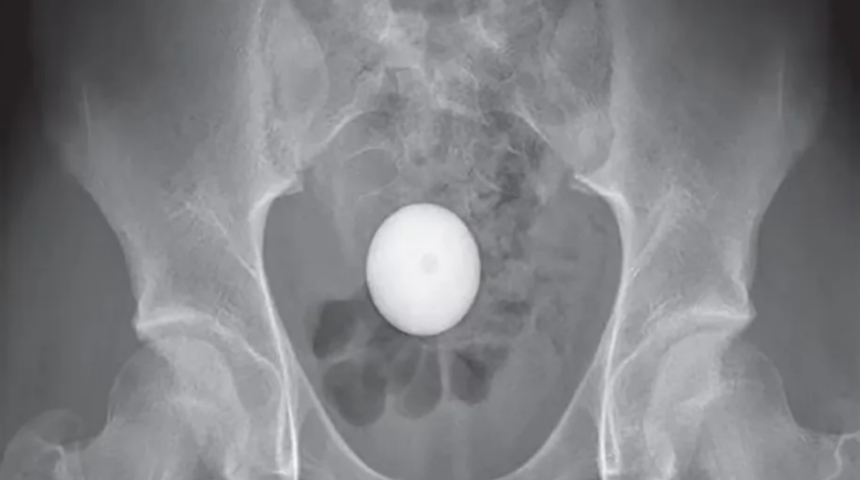

Hastanede yapılan müdahalelerin ardından X-ışınları, 14 yaşındaki çocuğun yuvarlak, beyaz bir yumurta ile deney yaptığını gösteriyor gibi görünse de, aslında kalın bağırsağın rektuma bağlanan son bölümü olan sigmoid kolonuna giden resimde görülen bir golf topuydu. Adı açıklanmayan çocuğun, dışkılayarak golf topunu elden çıkaramayınca paniğe kapıldığı ve annesine durumu bildirildi. Çocuk rapora göre herhangi bir rahatsızlıktan şikayet etmedi.

Doktorlar golf topunu çeşitli cihazlarla çıkarmaya çalıştı. Golf topunun "kendiliğinden rektuma gireceğini" umarak iki saatten fazla bir süre sonra "agresif" müdahaleleri bıraktıklarını bildirdiler. Ancak bir röntgen, 24 saat sonra bile hala orada olduğunu gösterdi.